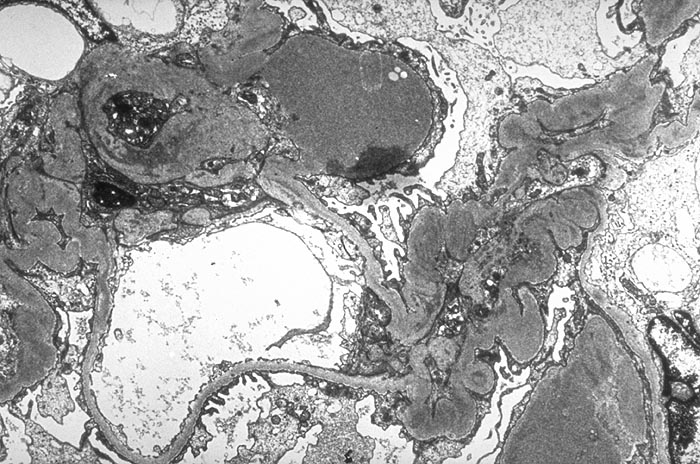

Membranoproliferative Glomerulonephritis: mesangiale Depots

Massive überwiegend mesangiale Depots. Die peripheren Glomerulusschlingen sind wenig verändert.

Keine IgA Nephritis.

Depots hauptsächlich subendothelial, in späteren Phasen auch mesangial, gelegentlich einzelne subepitheliale Depots. Wenn viele subepitheliale Deptos vorliegen=Typ III.